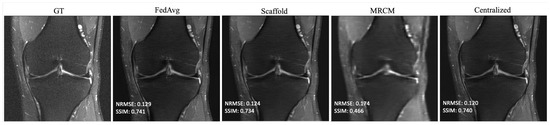

Based on the findings in Section 4.1, we selected 10 slices each from five different subjects, for a total of 50 local slices per client from the fastMRI dataset—this holds both for the i.i.d. and non-i.i.d. settings. The result of i.i.d. training is summarized in Table 2, which shows the average performance across all 10 sites that participated in training. For brevity, we report the average as we found that i.i.d. performance generally matched centralized training. All federated methods perform about the same or slightly better than centralized training in SSIM. The same is true with NRMSE. Centralized training and the federated unrolled optimization methods outperformed FL-MRCM. Figure 3 shows an example reconstruction for the i.i.d. case, comparing the ground-truth (GT) to FedAvg, Scaffold, FL-MRCM, and centralized training. Scaffold performed slightly better than FedAvg for this particular slice, and on-par with centralized, while FL-MRCM is poor, consistent with the results in Table 2.

Figure 3. Example reconstructions for knee PDFS 1.5T obtained in the i.i.d. client (knee PDFS 1.5T) scenario, and 240 communication rounds.

Bioengineering 10 00364 g003